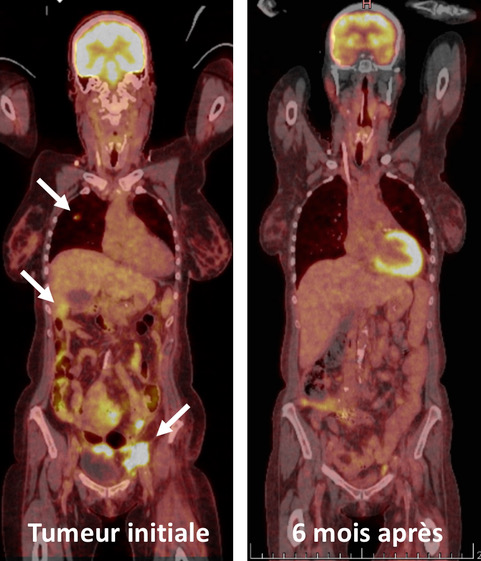

PET-CT-scanner montrant la tumeur du rein avec les métastases hépatiques et pulmonaires (gauche, flèches). PET-CT-scanner après la disparition complète des tumeurs à 6 mois (droite).